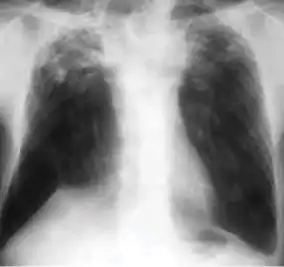

Chest x-ray showing patchy opacification on the upper right and mid-zone lung with fibrotic shadows, as well as bilateral hilar lymphadenopathy.